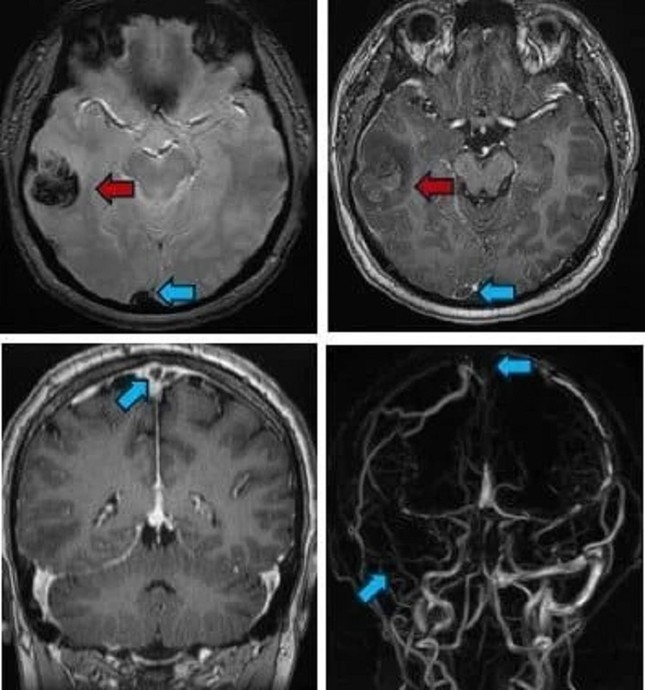

PGS.TS.BS Nguyễn Huy Thắng, Trưởng khoa Bệnh lý Mạch máu Não, Bệnh viện Nhân Dân 115 TPHCM cho biết, vừa tiếp nhận một thanh niên 22 tuổi (quê Cà Mau), nhập viện trong tình trạng đau đầu dữ dội. Kết quả chụp CT-scan cho thấy bệnh nhân bị xuất huyết não. Hình ảnh cộng hưởng từ phát hiện huyết khối tại nhiều vị trí trong hệ thống tĩnh mạch não của người bệnh.

Theo PGS Huy Thắng, đây không phải là trường hợp hiếm gặp. Huyết khối tĩnh mạch não (CVT) – tình trạng cục máu đông hình thành trong tĩnh mạch não là một biến chứng nguy hiểm liên quan trực tiếp đến việc hút shisha.